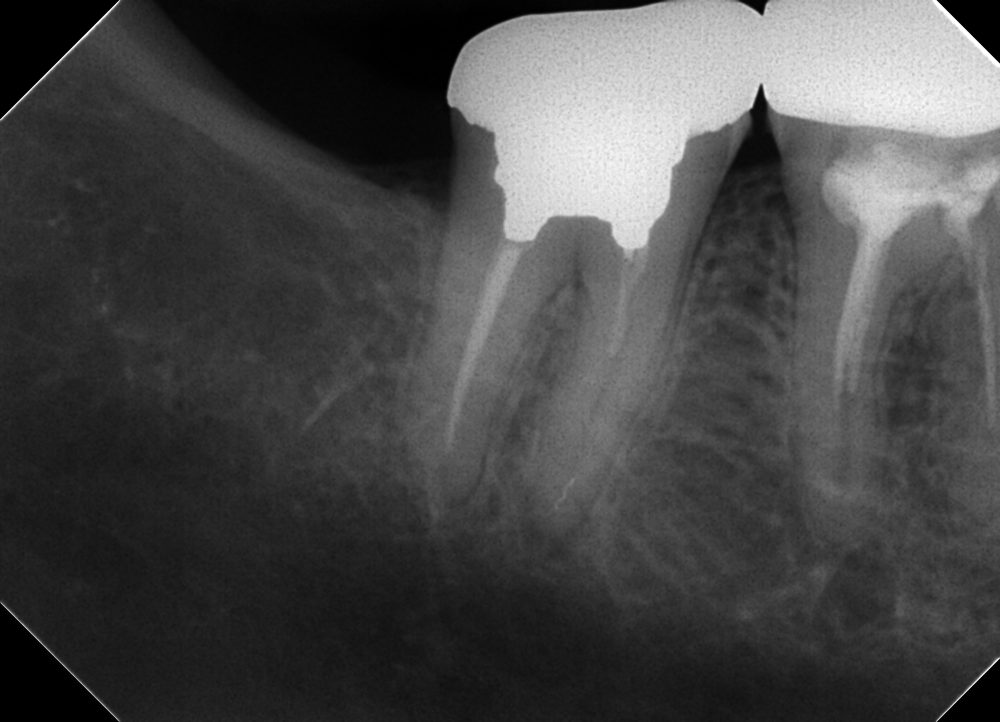

根の先の方で破折しているファイルを除去した症例

ここでファイルが折れています。

治療をすすめ、大体綺麗にした次の回が始まる前の状態のレントゲンです。

しっかりファイルが残っていますね。

折れているファイルがありますが、根の先まで器具を簡単に通すことが出来ました。バイパスと呼ばれています。

このケースは近心根が先の方でつながっているケースで、2本の神経管が合流する三角州のようなところにファイルがはまっているようでした。

遠心を根管充填した後にレントゲンを撮ったのは、患者様がファイルが残っているのをとても気にされていたので、当初、そのまま根管充填しようと考えたのですが、一応安心していただくために近心根を充填する前に撮影しました。(このまま充填すると取れたのかわからないレントゲンになってしまう)

根管充填後。

シーラーが少し根の外側にもれてしまいましたが問題ないと思われます。